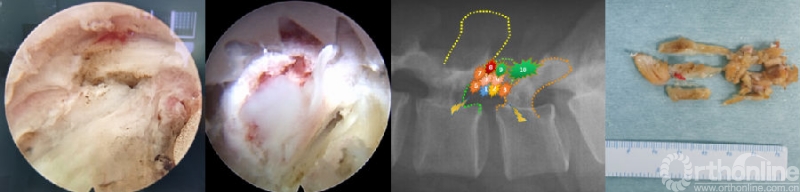

(9)椎间盘准备与终板处理

神经减压充分后,术野电凝止血,充分显露椎间隙后外侧,U套管向内适当牵开硬膜及神经根,T套管向外牵开软组织,用蓝钳或弧形骨凿锐性剪开纤维环至上下软骨终板,大小髓核钳预处理椎间盘组织,显露椎体上下边缘;对于椎间盘的处理可以采用多种工具,如U-T型双套管组合对软骨终板的旋切,可以在直视下整块切除软骨终板至终板下骨,结合方向的摆动,达到扇形的面积以及前方至前纵韧带,保证植骨面的充足。

目前效率更高的内镜融合处理套装已经成熟使用,如镜内铰刀、镜外铰刀、镜外方凿、镜外偏心刮刀等,均可全程直视完成椎间隙处理;如果椎间隙严重狭窄,还可以在U套管内采用开放手术的6-8号铰刀、椎间隙处理工具等盲视下处理,最后通过内镜来检查处理的效果。操作轻柔,避免损伤终板,是减少椎间融合器下沉、移位的重要环节。另外,行走根及硬膜腹侧的纤维环结构需要部分切除,以便于放置保护行走根的“舌形”工作套管。